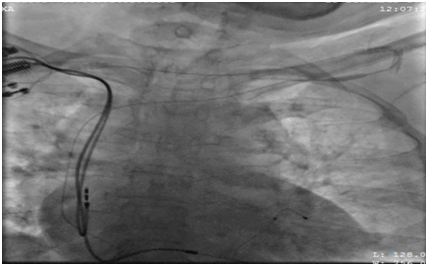

62 years old lady presented to the electrophysiology clinic with a history of shortness of breath, orthopnea, paroxysmal nocturnal dyspnea and lower limb swelling have started 3 weeks back. She denied any chest pain or syncope. She is known as HTN, IHD (S/P PCI to LAD 10 years ago), and History of Complete heart block (S/P DDDR pacemaker 6 years back). Previous LV function was normal (EF >55%, No significant valvular disease). On examination: She was conscious, oriented and vitally stable BP: 110/70 HR 70B/M, regular, RR: 22, Pso2: 96% on room air, T : 36.5, Congested neck vein observed, Chest: bilateral fine end in inspiratory basal crackles CVS: Normal S1, S2, no add sound or murmur Abdomen: Lax, soft, no masses Lower limb: Bilateral pitting edema ECG: well functioning paced rhythm; patient was diagnosed as new acute decompensate heart failure which was confirmed by ECHO showed: EF <35 %, with an impressive ventricular dyssynchrony, no significant valvular lesion, The patient was admitted in CCU as a case of ADHF (as a complication of RV pacing), was started on Ant failure treatment and the decision was taken to upgrade the DDDR TO CRTP. Then, Patient was driven in to Catha Lab. The procedure was initially attempted on the right, with successful cannulation of the right subclavian vein but unable to advance the guide wire to the superior vena cava (SVC), Venogram through the right anti-cubital vein showed a short occlusion of the right subclavian vein (Figure 1). The procedure was abandoned and LV lead implantation was performed on the left (Figure 2). Mild dissection of the coronary sinus occurred (Figure 3). Then sealed spontaneously and the LV lead was secured deeply in the posterolateral CS branch, a pair of long forceps were used for blunt dissection to create a subcutaneous tract from the right to the left. The proximal end of the LV lead was grasped with the forceps and tunneled above the sternum to rejoin the pocket (Figure 4). Then programming was done with good homeostasis.